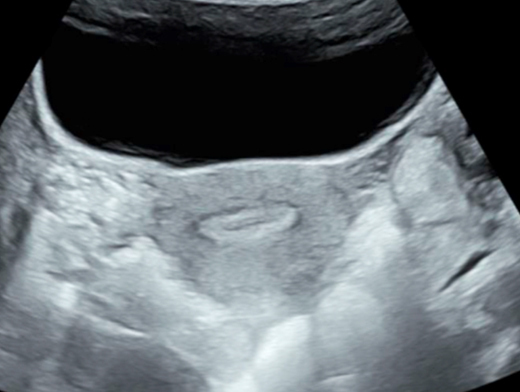

Mme G. est finalement césarisée sous anesthésie générale sans complication. Lors de l’hystérotomie, le liquide amniotique est sanglant avec de nombreux caillots. Les pertes sanguines sont estimées à 1 500 mL. L’équipe d’anesthésie a administré en peropératoire un culot de globules rouges et un plasma frais congelé (PFC), ainsi que de l’acide tranexamique. L’utérus est tonique en fin d’intervention. Au cours de la surveillance en salle de surveillance post-interventionnelle (SSPI), à quatre heures postopératoires, Mme G. a une barre épigastrique résistante aux antalgiques de palier 3. Les constantes sont les suivantes : pression artérielle = 190/110 mmHg ; fréquence cardiaque = 120 bpm ; saturation en oxygène = 99 % en air ambiant. Compte tenu de la tachycardie, vous réalisez une échographie transabdominale dont les images sont les suivantes. Figure 2a (Rodolphe Matias de Sousa, La Revue du Praticien)Figure 2b (Rodolphe Matias de Sousa, La Revue du Praticien)Figure 2c (Rodolphe Matias de Sousa, La Revue du Praticien) Vous décidez d’avancer le prochain bilan biologique et récupérez les résultats suivants : hémoglobine = 8,7 g/dL ; plaquettes = 40 G/L ; TP = 65 % ; TCA = 1,02 ; fibrinogène = 2 g/L ; haptoglobine indosable ; ASAT = 260 UI/L ; ALAT = 240 UI/L.

Pas d’hémopéritoine.

Concernant l’hématome sous-capsulaire du foie : Tableau 3 (Rodolphe Matias de Sousa, La Revue du Praticien) Concernant l’échographie transabdominale à la recherche d’un hémopéritoine :on regarde deux espaces, le cul-de-sac de Douglas entre l’utérus et le rectum, et l’espace de Morrison entre le foie et le rein. Figure 3a (Rodolphe Matias de Sousa, La Revue du Praticien)Figure 3b (Rodolphe Matias de Sousa, La Revue du Praticien)Figure 3c (Rodolphe Matias de Sousa, La Revue du Praticien) Pour rappel, concernant l’échographie en gynécologie : Figure 4a (Rodolphe Matias de Sousa, La Revue du Praticien)Figure 4b (Rodolphe Matias de Sousa, La Revue du Praticien)Figure 4c (Rodolphe Matias de Sousa, La Revue du Praticien)Figure 4d (Rodolphe Matias de Sousa, La Revue du Praticien)Figure 4e (Rodolphe Matias de Sousa, La Revue du Praticien)Figure 4f (Rodolphe Matias de Sousa, La Revue du Praticien)Figure 4g (Rodolphe Matias de Sousa, La Revue du Praticien)Figure 4h (Rodolphe Matias de Sousa, La Revue du Praticien)Figure 4i (Rodolphe Matias de Sousa, La Revue du Praticien)